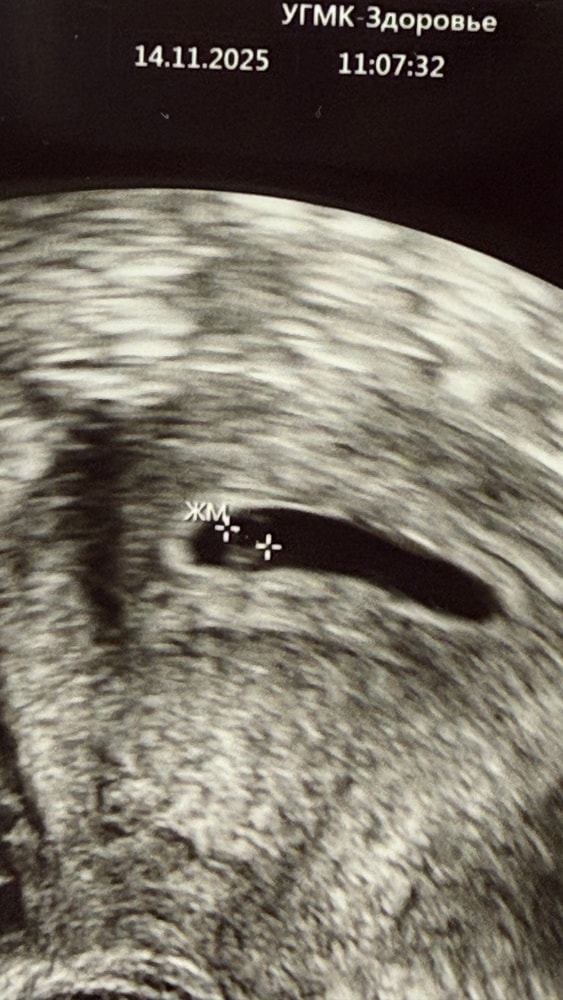

Первое УЗИ 22 ДПП

что имеем на 22 ДПП:

желточный мешочек 3,9 мм

эмбрион КТР 2,7 мм

сердцебиение визуализируется (но пока не слушали)

срок 5 недель 6 дней